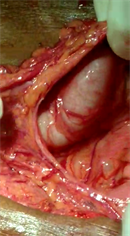

At laparotomy, pancreas was visualised through a rent in the greater omentum (Figure 2). The omentum was adherent to an organized hematoma at the

Figure 2. Shows the rent in the omentum and the dilated stomach.

OG junction, and this had caused an organoaxial volvulus. The volvulus was derotated, malignancy excluded and an anterior gastrojejunostomy with jejunojejunostomy was performed. The post operative period was uneventful and at 2 months follow up, the patient had gained 1 kg weight and the endoscopy was normal (stoma was healthy, the afferent and efferent loops functioning well)